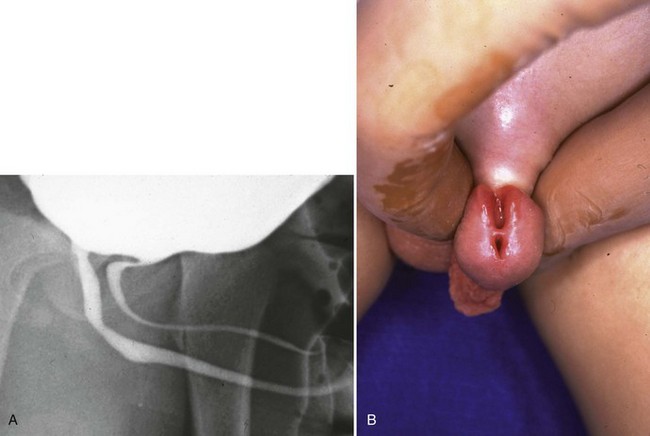

Anterior urethral obstruction is rare compared with posterior urethral valves. Although these obstructive structures may be called valves, they often occur in the form of a diverticulum of the urethra with one wall acting as an obstructive “valve” (Fig. 126–13) (Tank, 1987). There are also some reported cases of urethral flaps or valves in the anterior urethra (DeCastro et al, 1987; Scherz et al, 1987). The first case was reported in 1906, and the total number in the literature is small (Watts, 1906; Williams and Retik, 1969; Firlit et al, 1978).

Figure 126–13 A, Voiding cystourethrogram shows a severe case of anterior urethral valves. The bladder is almost empty, and there is massive reflux. The valve is in the form of a diverticulum. B, The filled diverticulum can sometimes be seen as a mass on the penis that resolves between voids. Pressing on the mass may express urine for some time after voiding.

Anterior urethral diverticuli typically occur where there is a defect of the corpus spongiosum, leaving a thin-walled urethra (Fig. 126–14). This segment of urethra balloons during voiding and causes a mass that is sometimes visible along the ventral wall of the penis. The mass resolves as urine drains from it between voids, and when full, urine can be expressed from the diverticulum by applying pressure. The distal edge of the diverticulum forms a flap that obstructs the flow of urine, and the effects of anterior urethral valves can be as damaging to the urinary tract as those of the posterior urethra. The embryology of these structures remains unclear but seems to be unrelated to the development of posterior urethral valves.